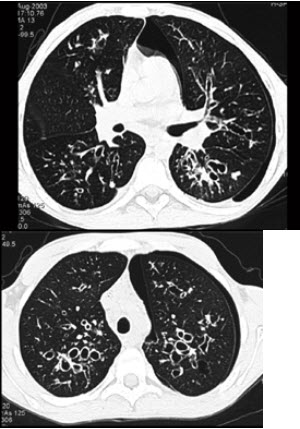

81、单项选择题

男,18岁,咳嗽,咳痰,咯血半月余,CT如图.选出最可能的诊断()

A.过敏性肺炎

B.支气管扩张

C.原发性肺结核

D.大叶性肺炎

E.肺癌